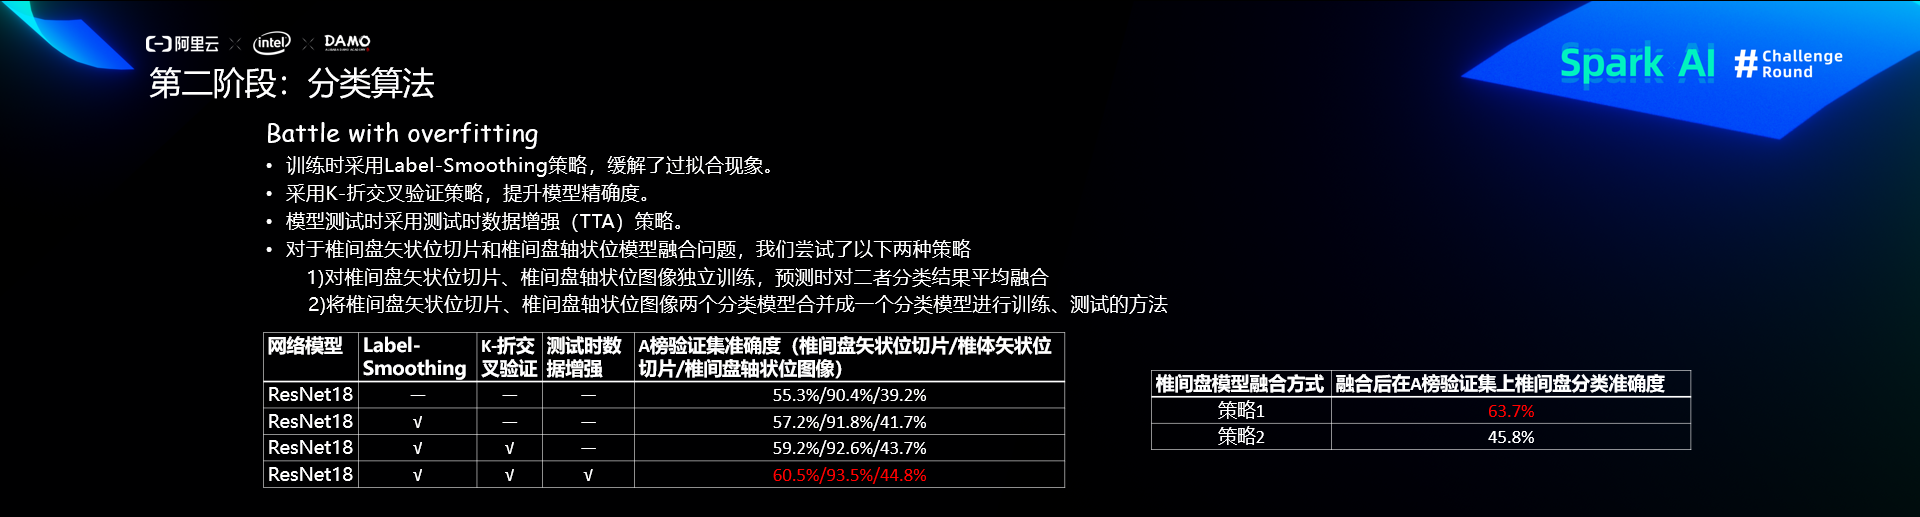

第二阶段:分类

分类算法